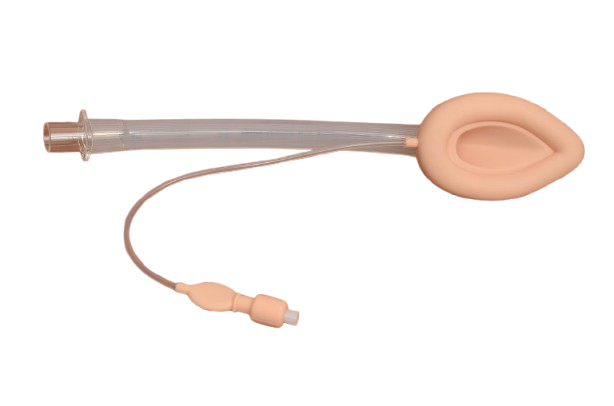

Laryngeal Mask Airway

Laryngeal Mask AirwayOur ProductsFrom SurgicaveUplode:9 months ago from India